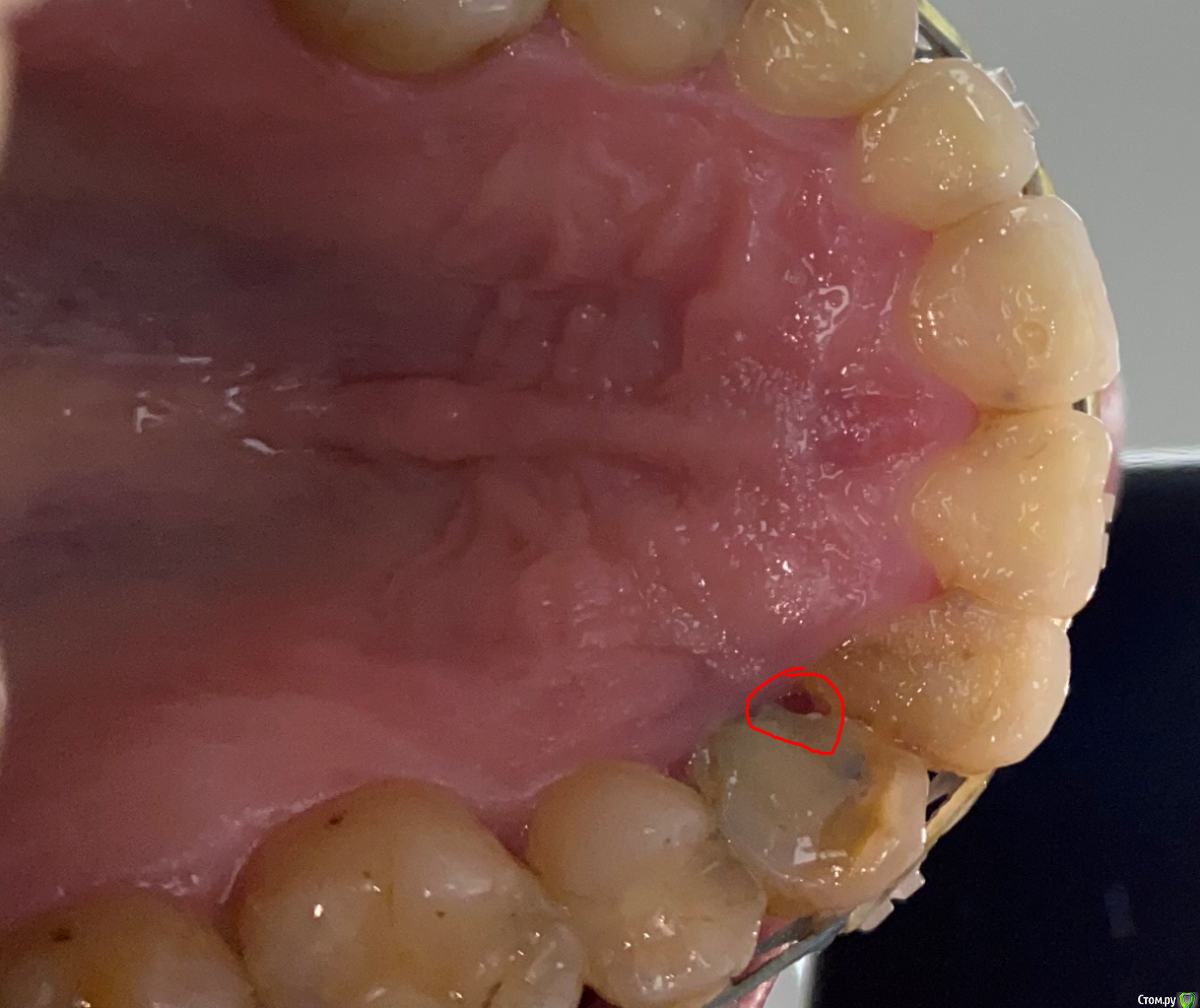

It'sGeorgy Опубликовано 4 июля, 2020 Поделиться Опубликовано 4 июля, 2020 Доброго времени суток!История такая: девушке (примерно 30-35 лет) в детстве был удален клык. После чего она перенесла 2 неудачных ортодонтии. Сейчас находится в процессе 3ьей попытки ортодонтического лечения. Пол года назад ситуация была такая: Сейчас такая: Котэ сделает в теч недели, прикреплю сюда же. Перкуссия 1.2 и 1.4 безболезненна. 1.4 без подвижности, 1.2 с I степенью подвижности. Само собой, как только снимут брекеты подвижность увеличится.Из личных мыслей: попробовать открыть, откюретажить корни, Эмдогейн, большой ССТ с бугра. Жду от этого небольшого прироста кости и "закрытия" кармана, чтобы внутрь перестала попадать пища.Всегда актуальный вариант: удаление обоих, мостовидная конструкция 1.1-1.5. Буду рад любым советам. Ссылка на комментарий

It'sGeorgy Опубликовано 4 июля, 2020 Автор Поделиться Опубликовано 4 июля, 2020 Проблема в плохих пломбах и гигиене. А также в ортодонтии пародонтита. Убирайте в топку брекеты и чистите зубки. ССТ закрывает рецессию, а не пародонтальный карман с анаэробами. Эмдогейн тоже сгниёт. Добейтесь ремиссии сначала. Ортодонту привет.Сразу уточню, что опыта ведения подобных пациентов у меня нет.Пол года назад, когда увидел пациентку впервые, именно ремиссии и попытался добиться. Сделали чистку, покюретажили. Сказали полоскать после приема пищи, купить ирригаторы. Оказалось бесполезно. Вчера пациентка сказала, что по ее мнению, не получается вычищать вот из-за этого участка. Возможно на фото не особо хорошо видно, но там огромное углубление:Собственно его я и хотел попробовать закрыть ССТ, отслоившись и подшив его небно. Спасибо за ваш совет. Будем начинать с чистки, снятия брекетов и замены реставраций. Если что-то интересное в итоге получится, скину результаты через пол года. Ссылка на комментарий